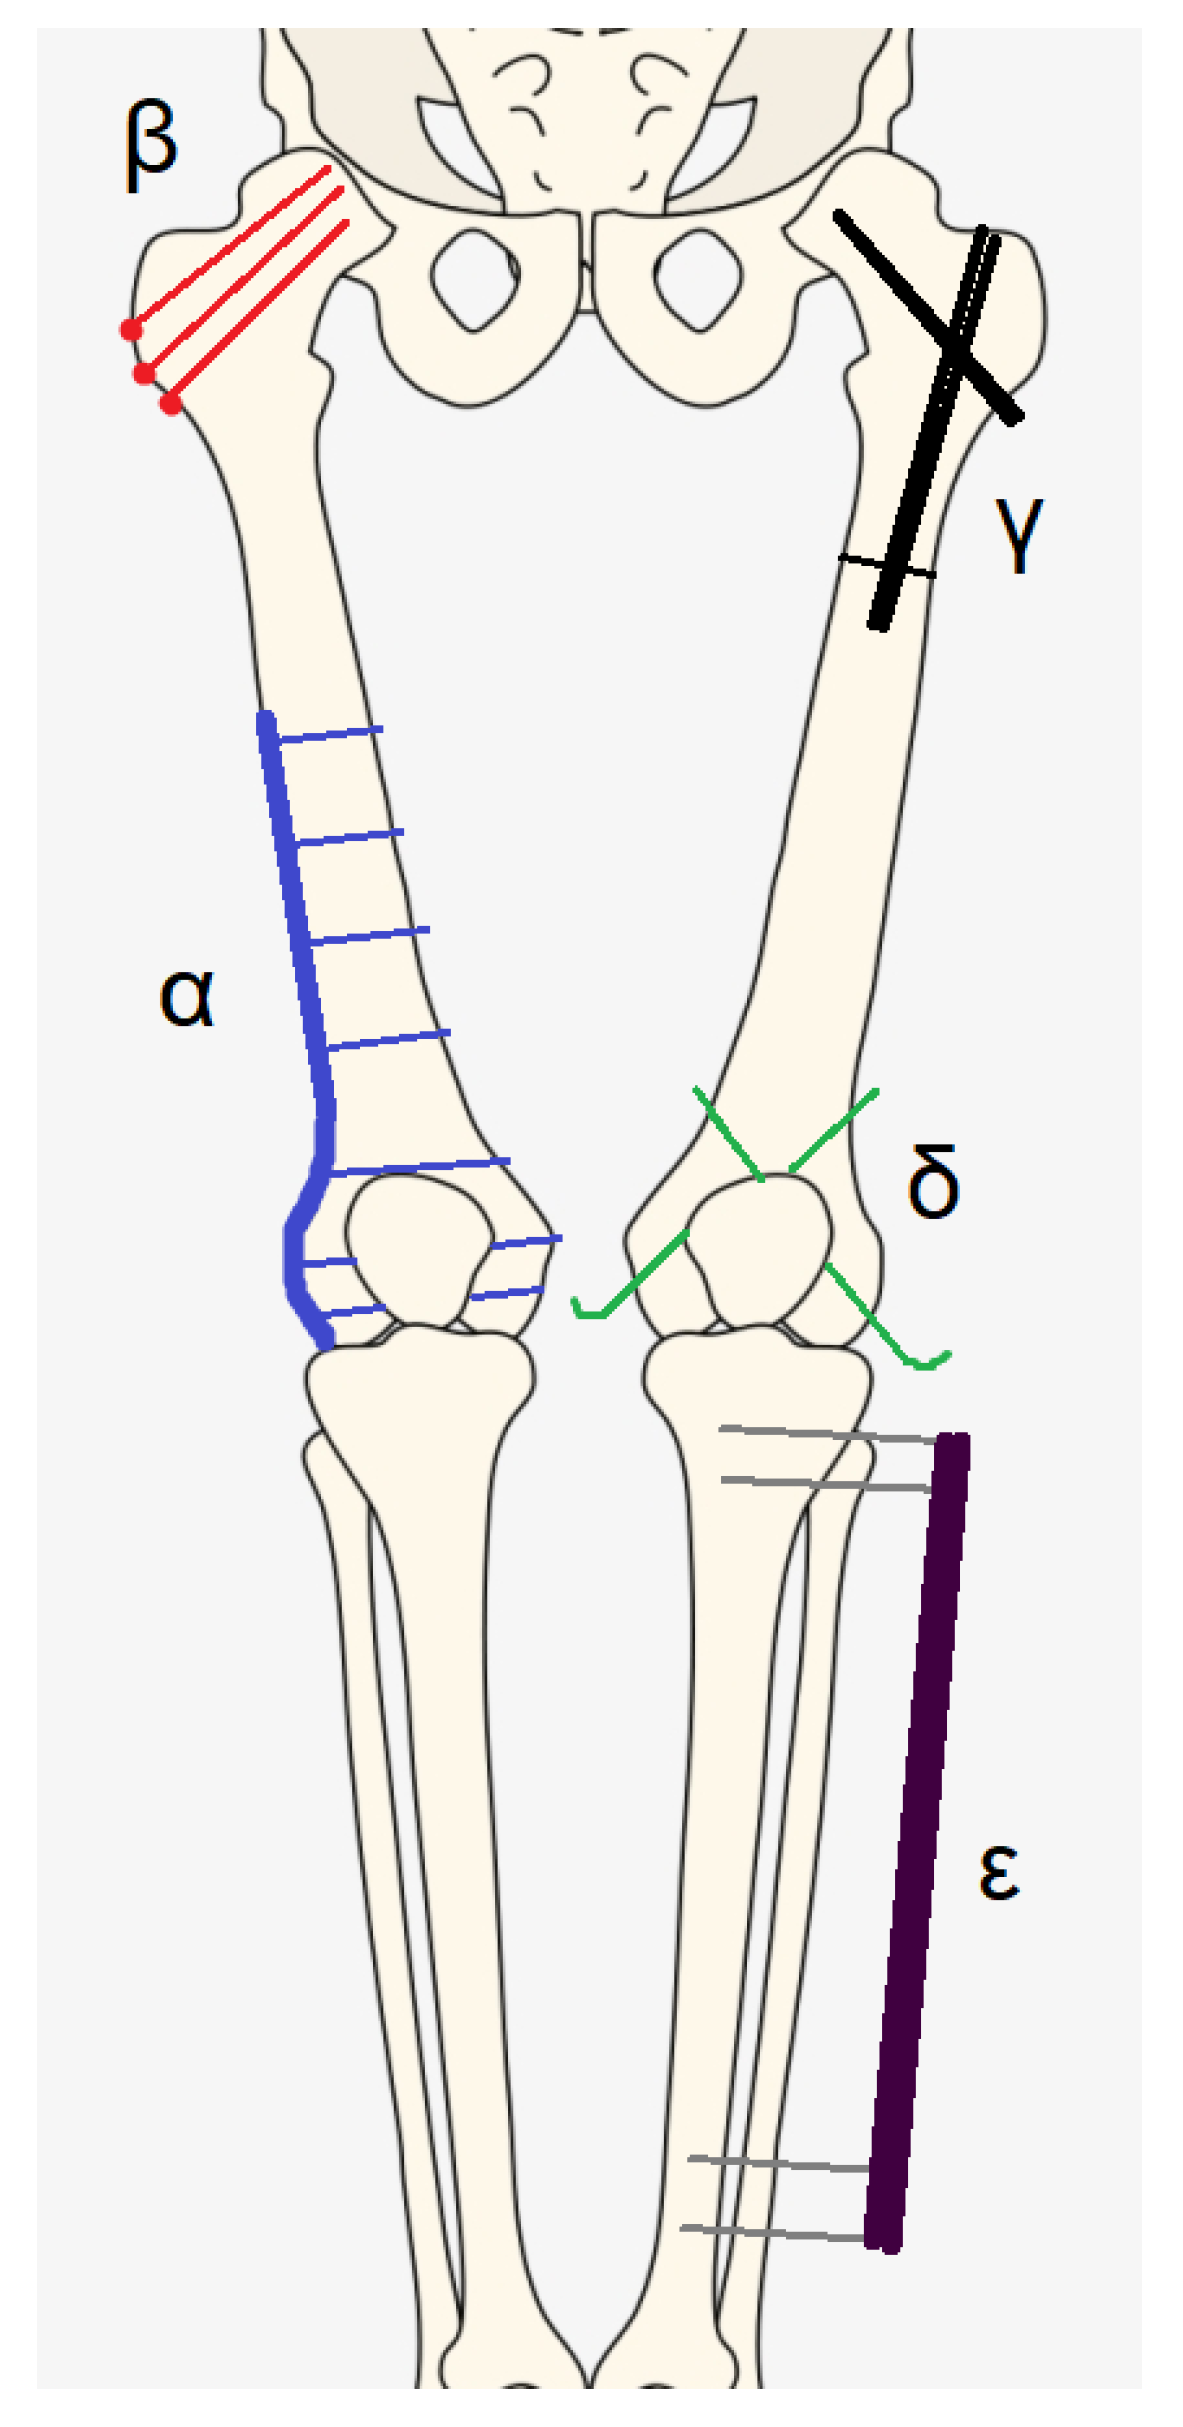

- HARDWARE

- α: plate and screws;

- β: screws;

- γ: nail;

- δ: K-wires;

- ε: external fixator.

| HARDWARE | Corresponding Letter of the Greek Alphabet |

|---|---|

| Plate and screws | Alfa (α) |

| Screws | Beta (β) |

| Nail | Gamma (γ) |

| K wires | Delta (δ) |

| External fixator | Epsilon (ε) |